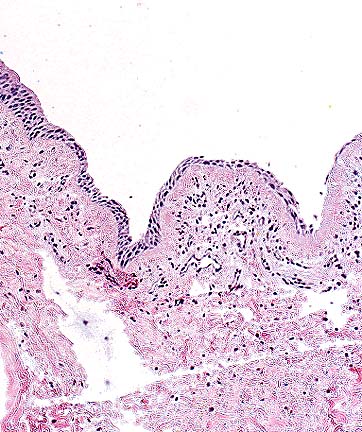

Diffuse severe pancreatic degeneration and loss in a farmed Atlantic salmon. (HE, 40X, 50K)

Skeletal muscle degeneration and atrophy with hypertrophy of satellite nuclei and moderate lymphocytic inflammation in a farmed Atlantic slamon. (HE, 400X, 54K)

Hyalin necrosis and atrophy of cardiac muscle with an infiltrate of low numbers of lymphocytes in a farmed Atlantic salmon. (HE, 200X, 45K)

Contributor's Diagnoses and Comments: Exocrine pancreas: Pancreatitis associated with severe necrosis of exocrine tissue and mild focal fibroplasia.

Heart: Myocardial necrosis, severe.

Red skeletal muscle: Hyaline necrosis, moderate.

Etiology: Pancreas disease: Atlantic salmon (Salmo salar).

There is marked loss of exocrine pancreatic tissue. A few foci of intact acinar tissue remain adjacent to islets of Langerhans and interlobular ducts. Loss of acinar tissue is associated with mild mononuclear cell infiltration and mild focal fibroplasia. Multifocal myocardial necrosis is also apparent. There is macrophage infiltration of necrotic fibers, vacuolation of the spongy trabecular ventricular myocardium and proliferation of endocardial cells. Moderate necrosis of the "red" skeletal muscle along the lateral line is apparent.

Pancreas disease (PD; polymyopathy syndrome; sudden death syndrome) causes major economic loss in the farmed Atlantic salmon industry in Europe. It can result in 10 to 50% mortalities and stunted growth in survivors. Until recently, the cause of PD was unknown. However, a toga-like virus has been recently isolated from affected fish (Nelson et al, 1995). Inoculation of this virus into healthy fish produces pancreatic, cardiac and skeletal muscle lesions similar to those seen in spontaneous outbreaks of PD. Studies of spontaneous outbreaks of the disease indicate that the initial lesion is acute pancreatic acinar cell necrosis and multifocal myocardial necrosis followed 2 to 3 weeks later by the development of skeletal muscle damage. It is speculated that the pancreatic and myocardial lesions may be the result of direct virus damage while the skeletal muscle lesions may have a viral and/or nutritional etiology.

AFIP Diagnoses: 1. Pancreas: Degeneration and loss, diffuse, severe, with subacute pancreatitis, steatitis, and serositis, Atlantic salmon (Salmo salar), piscine. 2. Heart, myocardium: Degeneration and necrosis, multifocal, moderate, with lymphohistiocytic myocarditis and endothelial cell hypertrophy. 3. Heart: Epicarditis, multifocal, lymphohistiocytic, moderate. 4. Skeletal muscle: Degeneration and necrosis, focally extensive, moderate, with fibrosis, lymphohistiocytic myositis and regenerative changes.

Conference Note: Pancreas disease is characterized by pancreatic atrophy with replacement by fibrosis and severe degeneration of cardiac and red skeletal muscle (aerobic skeletal muscle). The disease has been most reported in farm-raised salmon that have adapted to sea water (post-smolt). As the contributor notes, a togavirus has recently been identified as the cause of this disease.